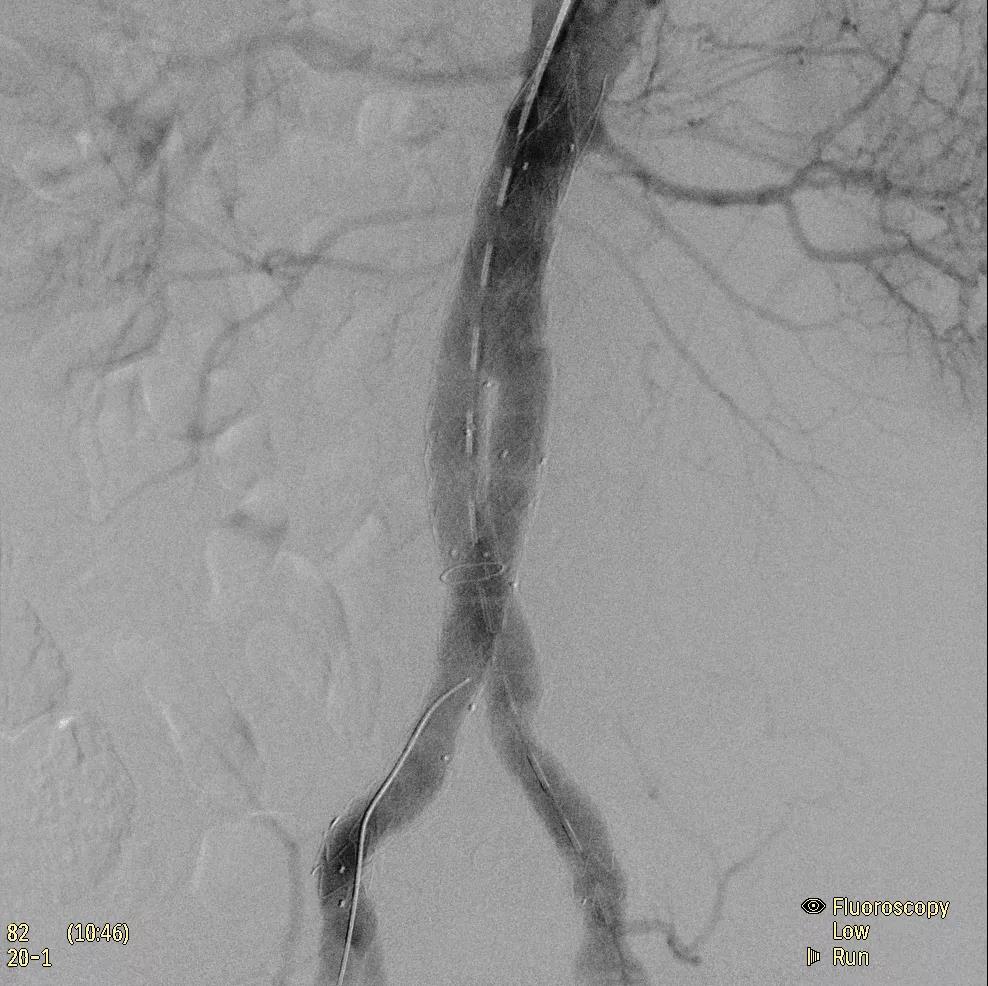

為了獲得清晰的高質(zhì)量圖像,Zenition 70 采用了與公司Azurion平臺(tái)相同的圖像處理算法,可提供患者解剖結(jié)構(gòu)的高清可視化和更大的可視區(qū)域。飛利浦的MetalSmart軟件等功能可確保圖像質(zhì)量,該軟件可自動(dòng)調(diào)整圖像的對(duì)比度和亮度,以便在視野中存在金屬物體(如植入物)時(shí)提高圖像質(zhì)量 - 這一特性使Zenition 70在整形外科中特別有用。